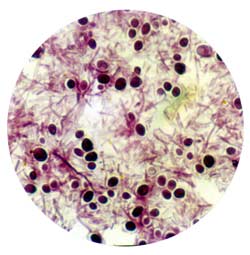

Грибковый возбудитель при легочном зигомикозе